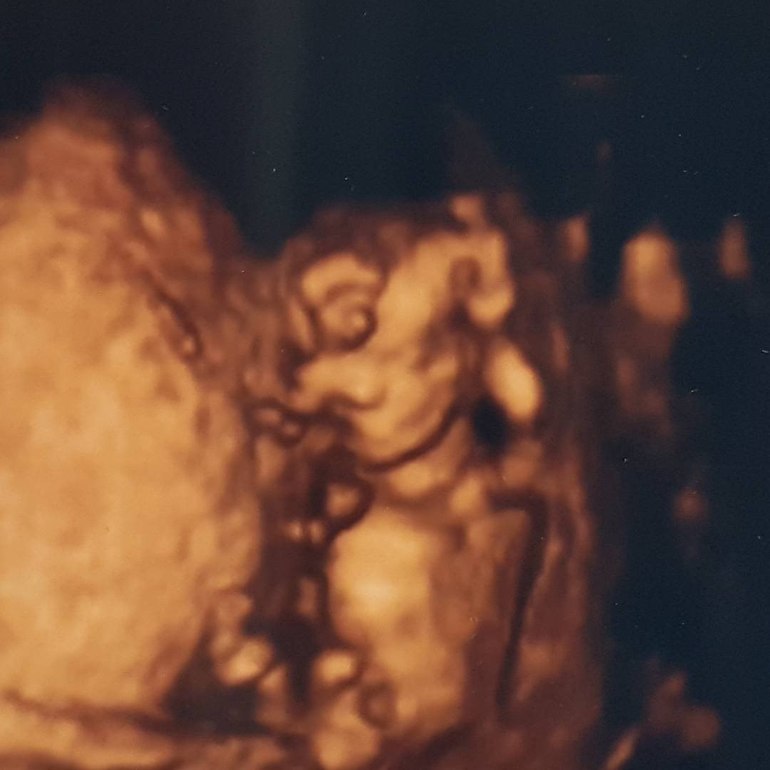

СкринингВсем привет! Нам уже 12,3 недель) В субботу были на первом скрининге! Это непередаваемые ощущения! Малыш заметно подрос по сравнению с последним узи в 9 недель и уже совсем как человечек)))

И вот наша КРАСАВИЦА (пока предположительно) 😍 😍 😍